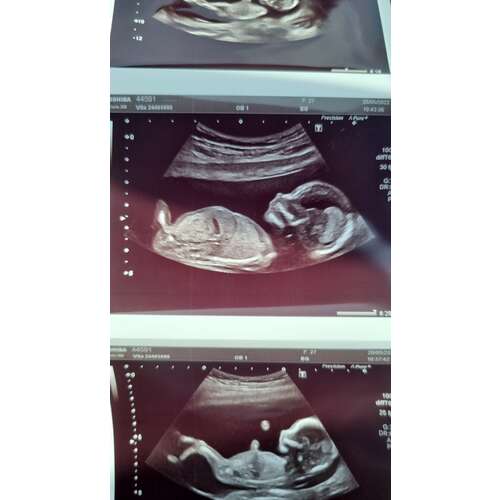

Is het op deze foto beter te zien? Meer foto's heb ik helaas niet🤔

Hier kan ik niet goed zien of ik nou naar de nub of het beentje kijk. Sorry. Had je binnenkort weer een echo?